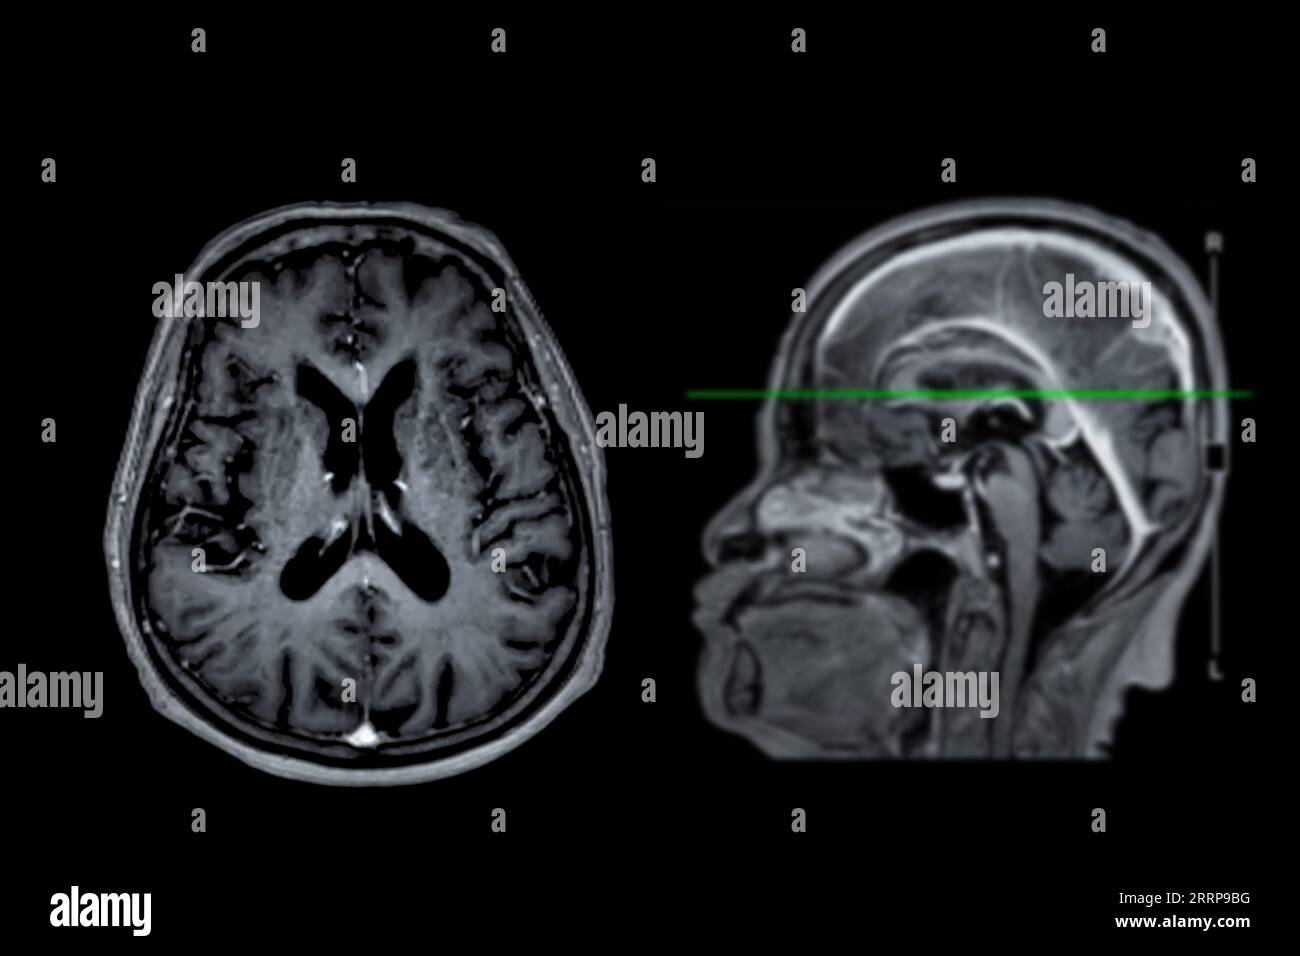

From www.alamy.com

MRI brain scan Axial and sagittal view with reference line for detect What Can Brain Mri Detect That Ct Cannot Bones, stones, blood, organs, lungs, cancer stages and abdominal emergencies. Ct scans are the most common. A variant called mr angiography (mra). An mri scan can be used to examine almost any part of the body, including the: Internal organs, such as the liver, womb. Where mri really excels is showing certain diseases that a ct scan cannot detect. Some. What Can Brain Mri Detect That Ct Cannot.

MRI brain scan Axial and sagittal view with reference line for detect What Can Brain Mri Detect That Ct Cannot Understand their pros and cons along with general guidelines that doctors use to decide between head ct and mri. Mri can detect abnormalities that might be obscured by bone with other imaging methods. Internal organs, such as the liver, womb. A variant called mr angiography (mra). Some cancers, such as prostate cancer, uterine cancer, and certain liver cancers, are pretty. What Can Brain Mri Detect That Ct Cannot.

From justinboey.com